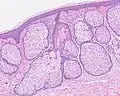

Sebaceous hyperplasia shares histopathological similarities with the typical architecture of the folliculosebaceous unit, but with larger and expanded sebaceous glands.[12][13]

H&E staining of biopsied lesion of sebaceous hyperplasia: Note the multiple, mature sebaceous lobules attached to the central dilated duct in the upper dermis.

H&E staining of biopsied lesion of sebaceous hyperplasia: Note the multiple, mature sebaceous lobules attached to the central dilated duct in the upper dermis. -